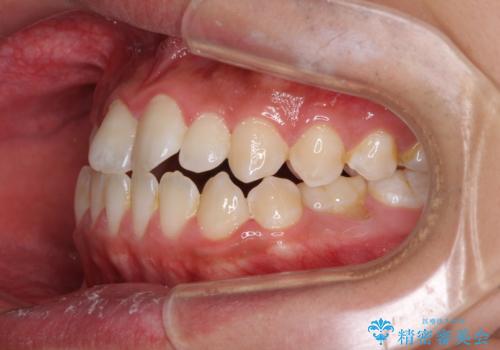

- 受け口傾向の咬み合わせと口元の突出感を気にして来院された患者様です。

受け口傾向特有の狭い上顎歯列であったため、歯列の拡大を補助装置で行い、下顎歯列全体を後方に移動させることとしました。

奥歯の咬み合わせを改善させた後、上下左右の小臼歯(下顎は残存乳歯)を計4本抜歯し、ワイヤー装置にて口元の突出感を改善しながら咬み合わせを整えることとしました。